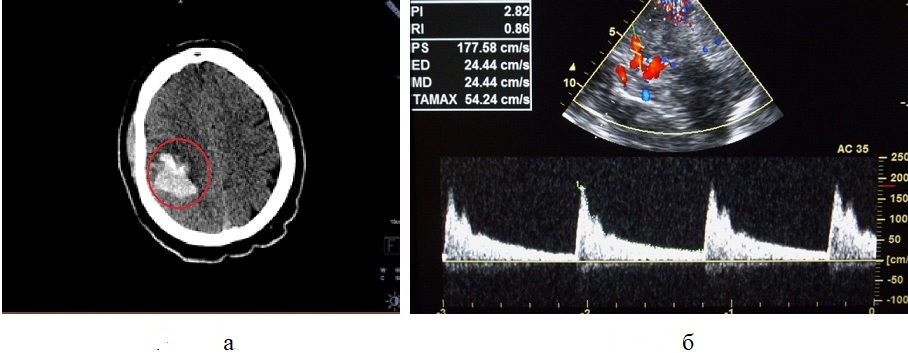

Рисунок 5 - Пациент С., 58 лет, с ишемическим инсультом после сочетанного применения тромболитической терапии и тромбэкстракции, осложнившегося геморрагической трансформацией очага ишемии

Примечание: а – Мультиспиральная компьютерная томография головного мозга без контрастного усиления в аксиальной проекции; геморрагическая трансформация очага ишемии в конвекстиальных отделах лобной и теменной долей справа (круг); б – Транскраниальное дуплексное сканирование артерий головного мозга через височное окно; увеличение пиковой систолической скорости кровотока до 177 см/с и повышение индексов периферического сопротивления (RI=0,86; PI=2,82) в правой СМА у пациента с геморрагической трансформацией очага ишемии